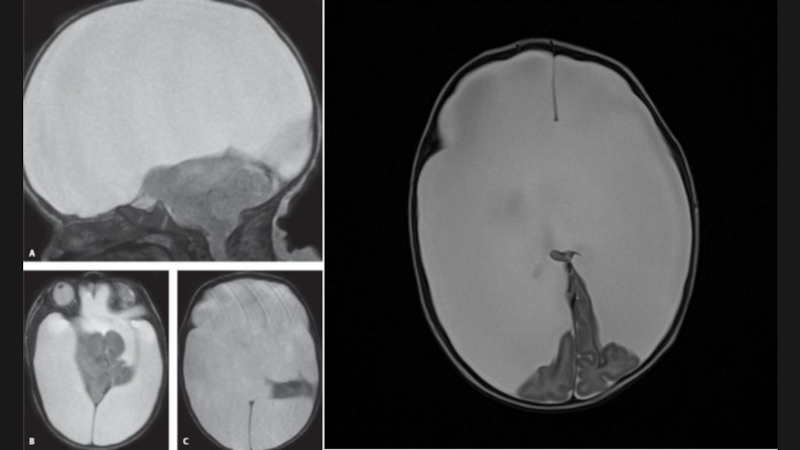

Слайд 38Мальформация Dandy-Walker

Данная мальформация представляет собой кистозное расширение IV желудочка,

сочетающееся с агенезией червя мозжечка, высоким расположением мозжечкового

намета и гидроцефалией

“Классическая” МДУ:

-кистозная дилатация IV желудочка - увеличенная ЗЧЯ;

-гипоплазия червя мозжечка, его краниальная ротация;

Гипоплазия червя мозжечка c ротацией(ГЧР):

-непостоянная гипоплазия червя мозжечка,

-ЗЧЯ/ствол мозга нормальных размеров,

-киста небольшая или отсутствует;

Персистирующая киста кармана Блейка(ККБ):

-сообщение “открытого” IV желудочка с кистой;

Мега цистерна магна(МЦМ):

-увеличенные околомозжечковые цистерны сообщаются с базальными субарахноидальными пространствами.

Мальформация Dandy-WalkerДанная мальформация представляет собой кистозное расширение IV желудочка,   сочетающееся с агенезией червя мозжечка, высоким